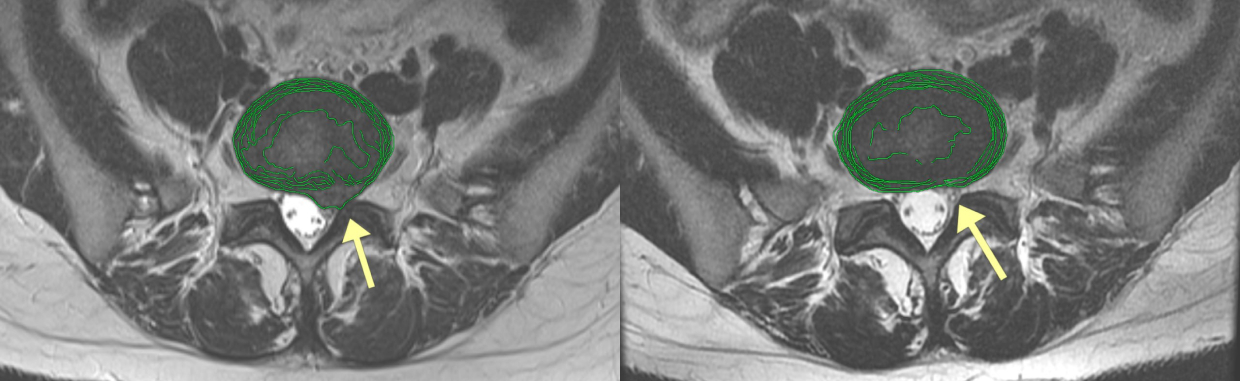

Результаты лечения наших пациентов подтверждаем на МРТ

94% пациентов вылечились без операции.

До лечения

Пациент 38 лет.

— Первое обострение (1 снимок) с прострелом в спине и болью в ноге и ягодице до 6 баллов в течение 1 мес.

— Самостоятельная попытка справится с болью с помощью упражнений в течение 1 мес.

— Второй прострел в спине и усиление болей до 9 баллов в состоянии покоя. Обратился в клинику.

После лечения

Полная резорбция грыжи диска и соответствующее исчезновение болей. Возврат к привычному образу жизни (3 снимок).